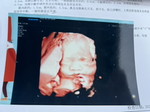

การตรวจดาวดาวน์ซินโดรม

มีแม่ๆท่านไหนที่ตั้งครรภ์ 13+wแล้วยังไม่ไปตรวจบ้างค่ะ ถ้าตรวจช้ากว่านี้จะมีอันตรายกับลูกในท้องมั้ยค่ะ

ไม่ช้านะคะ เราได้ตรวจตอน 14 วีคค่ะ พี่ๆพยาบาลบอกว่า ตรวจดาวน์ ต้องเริ่มตรวจตอน 14วีคขึ้นไปค่ะ